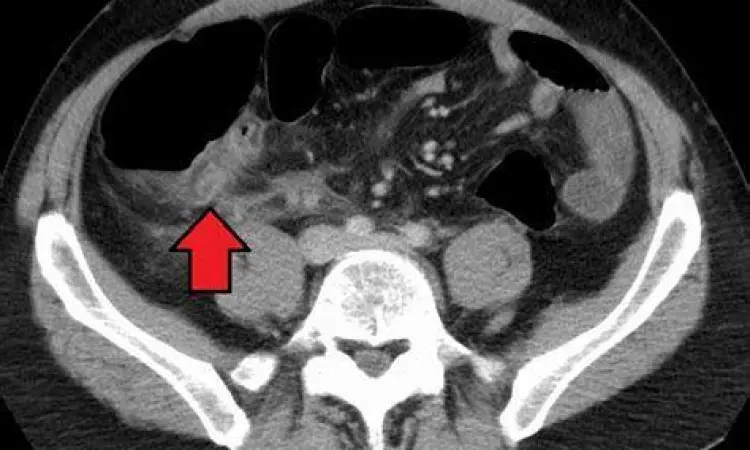

Metode Diagnosis dan Penanganan Medis

Jika Anda merasakan ciri usus buntu seperti yang dijelaskan di atas, dokter akan melakukan serangkaian tes untuk mengonfirmasi diagnosis. Langkah pertama adalah pemeriksaan fisik, termasuk tes Rovsing (nyeri di kanan bawah saat perut kiri ditekan) dan tes Psoas. Selain itu, tes darah lengkap akan dilakukan untuk melihat kenaikan jumlah sel darah putih (leukosit) yang menandakan infeksi. Metode pencitraan seperti USG abdomen atau CT Scan adalah standar emas untuk melihat kondisi usus buntu secara visual. Jika diagnosis positif, tindakan paling umum adalah apendektomi, yaitu operasi pengangkatan usus buntu. Saat ini, prosedur ini banyak dilakukan dengan teknik laparoskopi (lubang kunci) yang memiliki masa pemulihan jauh lebih cepat dibandingkan operasi terbuka konvensional.